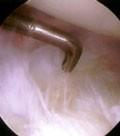

Tratamiento quirúrgico… • INDICACIONES: • Si sintomas persisten a los 3 meses de tto. Conservador • Perdida progresiva de la funcion del hombro • debilidad REPARACION QX: RUPTURA PARCIAL ARTROSCOPIA

Indicaciones artroscópicas.. • Ruptura parcial del manguito • Minimo trauma a tejidos blandos • Rehabilitación mas precoz • Menos complicaciones

Cirugia abierta

Los reparos de rupturas completas del manguito rotador requieren una pequeña incisión lateral para reinsertar los tendones.

consiste en secar la bursa subacromial y de acuerdo a los hallazgos intraoperatorios, se hace una acromioplastia y una resección del ligamento acromiocoracoideo.

Hay dos escuelas:

La primera debrida los bordes de la lesión y hace una acromioplastia; otros prefieren reparar el defecto y decomprimir el espacio subacromial

Artroscopia